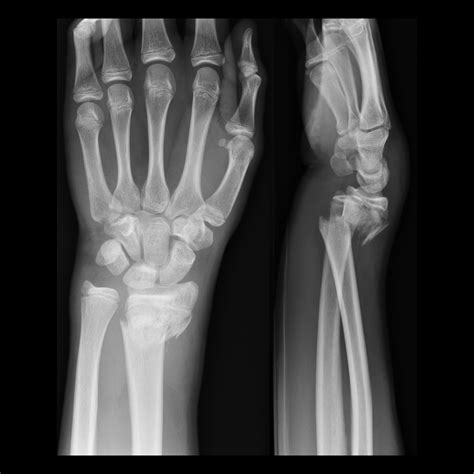

Comparing Colles Fracture vs Smith Fracture

While both Colles Fracture and Smith Fracture involve the distal radius, they have distinct differences in terms of mechanism, appearance, and treatment. Here is a comparison of the two:

Feature Colles Fracture Smith Fracture

Mechanism of Injury Fall onto an outstretched hand with the wrist in extension. Fall onto a flexed wrist or direct blow to the dorsum of the wrist.

Direction of Displacement Dorsal (towards the back of the hand). Volar (towards the palm of the hand).

Common Deformity "Dinner fork" deformity. "Garden spade" deformity.

Treatment Options Closed reduction and immobilization, ORIF for severe cases, physical therapy. Closed reduction and immobilization, ORIF for severe cases, physical therapy.

Understanding these differences is essential for accurate diagnosis and appropriate treatment. Both fractures require prompt medical attention to ensure proper healing and to minimize long-term complications.